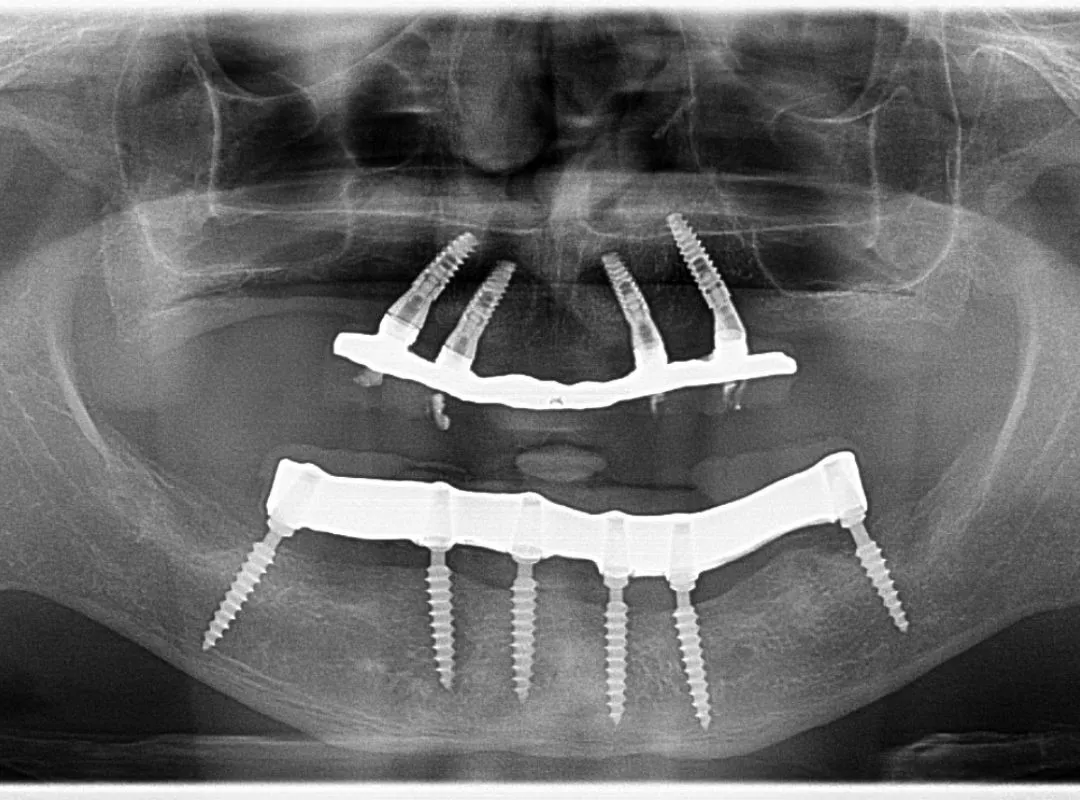

Dental Implants Advanced, long-lasting solutions to replace missing teeth with precision and aesthetics.

I had my dental implants done at the clinic. The process was done very well and the implants are performing exceeding well. The team is meticulous and delivers superlative performance .